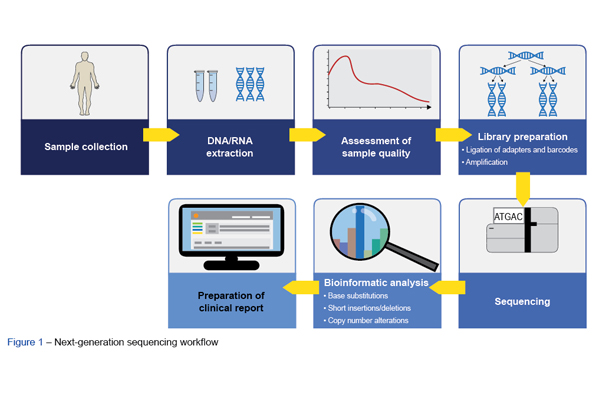

Na área da oncologia clínica, a sequenciação de nova geração (NGS) foi implementada com o objetivo de contribuir para o diagn...